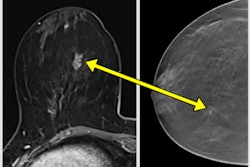

MRI remains the gold standard for the diagnosis of breast implant rupture, but ultrasound can also be a useful screening tool in the initial assessment of implant integrity, U.K. researchers noted at the recent European Society of Breast Imaging (EUSOBI) annual meeting.

"Implant rupture can be intracapsular or extracapsular, depending on the location of the ruptured silicone/saline in relation to the fibrous capsule," they explained.

"As the study demonstrates, ultrasound can be used as screening tool by expert operators to check for implant integrity. In case of doubt or suspicion of implant rupture, MRI should be performed," Giannotti said.